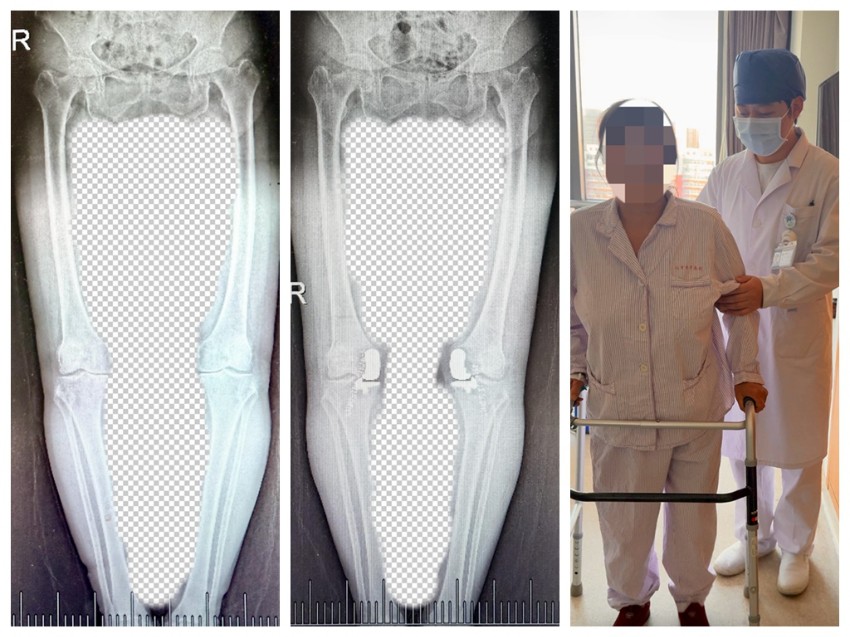

近日,北京电力医院骨一科成功为一名患者实施院内首例双膝一期保膝单髁置换手术,标志着科室在保膝微创治疗领域实现突破性进展。

63岁的患者因双膝疼痛迁延不愈,慕名到北京电力医院骨一科找到康建国主任医师就诊。此前她曾咨询多家医院,均建议她接受关节置换手术。骨一科崔准副主任组织关节外科团队进行了病例讨论与分析,根据患者具体情况和患者意愿,最终决定行“双膝一期保膝手术:双膝单髁置换手术”。手术在崔准主任医师带领下,康建国主任医师主刀同期完成双侧关节病变区域的微创修复重建,最大程度保留了患者自身关节的结构和功能,减少了创伤与恢复周期,手术无需输血,而且术后第一天即刻下地活度。

术后患者关节功能恢复顺利,对手术效果及康复进度均表示满意。此手术的成功开展,既是骨一科技术实力的体现,也为膝关节疾病患者提供了更精准、更贴合个体需求的治疗选择。